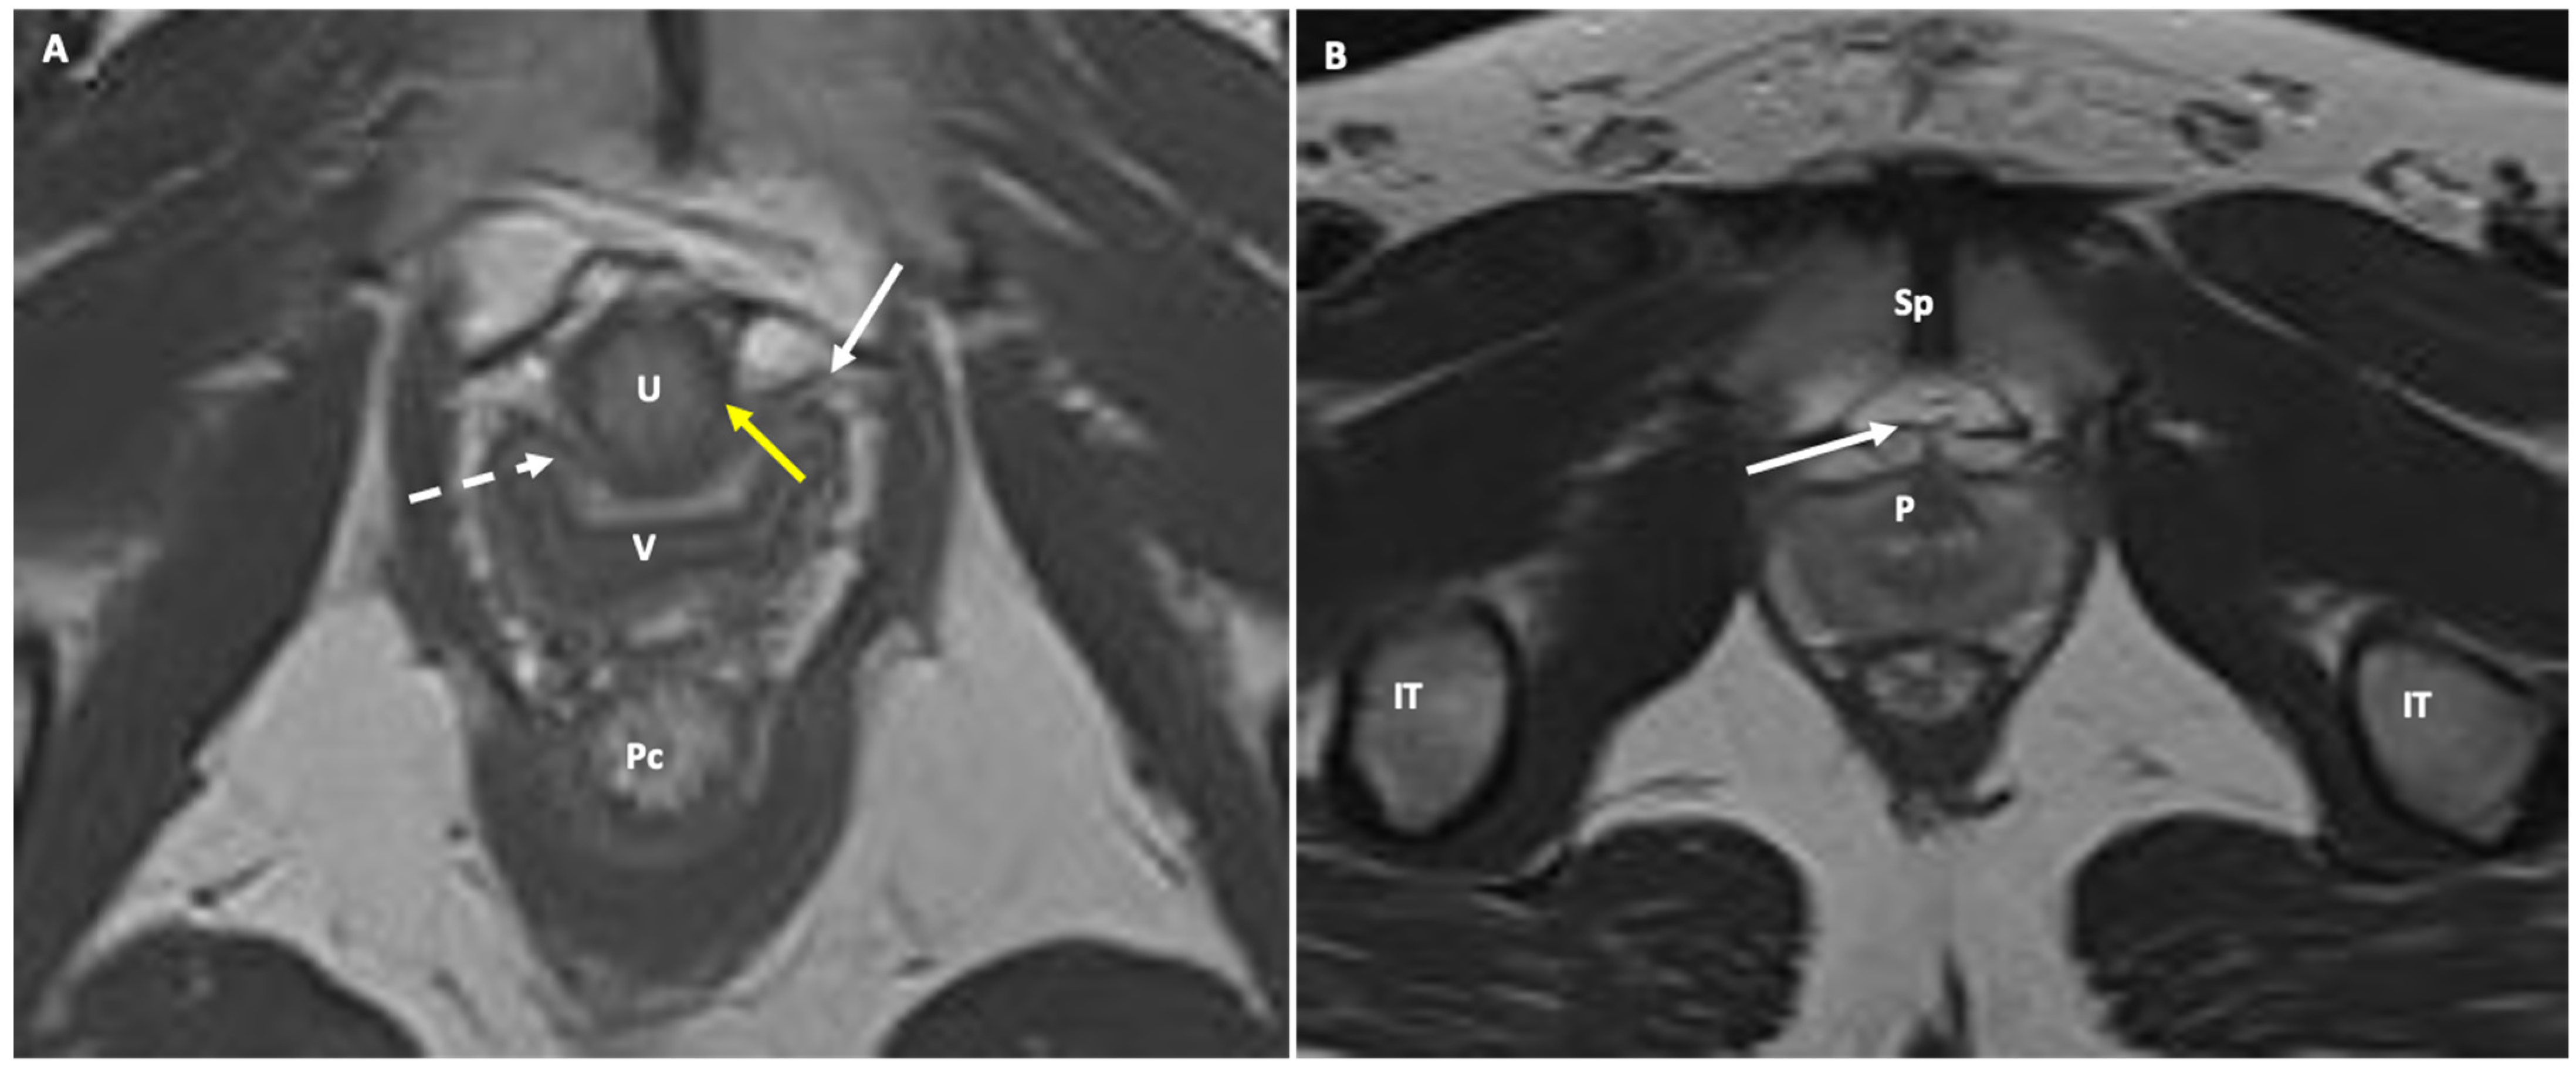

- Female urethra: This appears as a target-like structure, showing a central hypointense inner ring, which indicates the muscularis mucosa. Surrounding this is a middle, thicker ring of intermediate signal intensity, resulting from a combination of submucosa, longitudinal, and circular smooth muscle. The third, thinner hypointense outer ring represents the striated sphincter muscle. The surrounding space shows high signal intensity, representing connective tissue and smooth muscle within a highly collagenized vascular matrix. Within this space, three distinct ligaments can be identified at specific points along the urethra. At the 30th percentile, the periurethral ligament is visible as a thin hypointense linear structure originating from the medial aspect of the puborectal muscle, running ventrally to the urethra. The paraurethral ligament appears as a slightly oblique hypointense structure connecting the lateral wall of the urethra to the periurethral ligaments (Figure 4). At the 50th percentile, the pubourethral ligament is visible as a hypointense structure connecting the lateral aspect of the urethra to the arcus tendineus fasciae pelvis. In young males, corresponding structures may occasionally be visible in the retropubic space, just anterior to the prostate apex. On sagittal T2-weighted MR, the urethra appears as a cylindrical structure extending from the bladder neck to the external meatus. The signal intensity mirrors that described above, with the internal meatus as the zero point and the external meatus at the 100th percentile.

- Anal sphincter complex: This shows variable composition and signal intensity on axial T2-weighted images depending on the level. The upper part consists of the internal sphincter, longitudinal muscle, and puborectal muscle. The middle part features the intersphincteric space, which appears as a high-signal-intensity, slit-like space between the internal sphincter (5 mm thick, intermediate signal intensity) and the external sphincter (1.5 mm thick, low signal intensity). A thin hypointense circular structure within this space represents the longitudinal muscle, which is a continuation of the outer longitudinal smooth muscle of the rectum. The lower part contains the external sphincter and the longitudinal muscle layer. On mid-coronal T2-weighted images, the thicker inner layer is formed by the two halves of the internal sphincter in apposition, while the intersphincteric space is visible as a thin, high-signal-intensity layer. At the outer margin, a cleft divides the puborectalis muscle (above) from the external sphincter (below). On midsagittal T2-weighted MR images, the anal sphincter appears as a low-signal-intensity, homogeneous, cylindrical structure, approximately 4 cm long, composed of muscle layers extending from the attachment of the levator ani muscle to the rectum. Lastly, the perianal spaces are clearly seen as two symmetrical, high-signal-intensity, fat-containing, pyramid-shaped spaces surrounding the hypointense anal canal, with multiple fibrous septa. The apex is visible at the origin of the V-shaped levator ani muscle, along with the supralevator space above it.